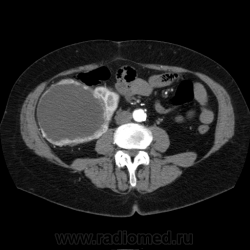

Солитарное кистовидное образование правой почки с неравномерно утолщенными стенками, у узлами в капсуле, накапливающими контраст. Фасция Гарота справа тяжистая. По классификации - киста 4-й категории, крайне велика возможность малигнезации. Может, показалось вовлечение парааортальных лимфоузлов?

В 1986 г. M.A. Bosniak создал “рабочую” классификацию кистовидных образований почек, которая позволяет предположить доброкачественность или злокачественность кистозных образований при распределении их по радиологическим критериям на 4 основные категории. Образования I и II категорий являются заведомо доброкачественными и поэтому нуждаются в динамическом наблюдении или, по показаниям, в лечебной пункции со склеротерапией под контролем УЗИ или КТ. Образования III категории могут быть как доброкачественными, так и злокачественными, а образования IV категории – кистозные почечноклеточные раки.

Третья категория – более сложные кистовидные образования, которые демонстрируют какие-либо радиологические признаки злокачественности. Некоторые из этих образований оказываются доброкачественными (например, сложные кисты, мультилокулярная кистозная нефрома, геморрагические кисты), другие злокачественными (почечные кистозно-клеточные карциномы). Одним из критериев, которые заставляютотнести кистовидное образование почки к III категории, является повышение плотности ее стенки. При КТ у кистовидного образования выявляется плотная (вплоть до обызвествления) стенка по всему периметру кисты, хотя образование может сохранять некоторые признаки простой кисты почки. Следующим критерием является характер отложения кальцинатов. Если при КТ в образовании определяется большое количество кальцинатов, расположенных глыбками (как на периферии образования, так и в центре), если из-за этого стенки и перегородки становятся утолщенными, неправильной формы, то данное образование следует отнести к III категории. Наличие множественных перегородок толщиной более 1 мм, видимых утолщений в месте прикрепления перегородок к стенкам кисты позволяет также отнести данное образование к третьей категории. Большое количество тонких перегородок в образовании определяет его как сложную кисту. Такие образования крайне сложно дифференцировать как доброкачественные или злокачественные, но они чаще по КТ-картине выглядят как злокачественные. При КТ определяется негомогенное многокамерное образование округлой или неправильной округлой формы, возможно с капсулой. Плотность образования неоднородная, пониженная относительно паренхимы, в полости образования видно большое количество перегородок.

IV категория – поражения явно злокачественные, обычно кистозные почечно-клеточные карциномы. Основными симптомами кистозной опухоли при КТ являются: неправильная форма кисты, негомогенность структуры образования с участками некроза, деформация почки, нечеткая граница между кистой и паренхимой почки, плотностные показатели могут быть выше, чем в кистах (+20…+40 Н), т.е. близкие к плотности почечной паренхимы. Капсула имеет неравномерную толщину, часто обызвествлена по периферии. Возможна визуализация дополнительных фокусов образования (кажущееся увеличение образования в размерах и изменение его конфигурации) после введения контрастного вещества. Но самым важным симптомом является увеличение плотности внутреннего содержимого после внутривенного введения контрастного вещества. Часто на серии срезов удается выявить эндофитные гребневидные фестончатые разрастания, выступающие в просвет кистозной полости. Особенно хорошо этот мягкотканый васкуляризированный компонент опухоли проявляется при внутривенном контрастировании

Всё верно, я тоже пользуюсь данной классификацией по Босняку, кистозно-солидное образование правой почки я отнёс к 4 категории, нужно отметить, что преобладает кистозный компонент, но солидный компонент довольно приличный и значительно накапливает контрастное вещество до 80-90HU, четко капсулу образования не отграничить. Ко всему этому в паренхиматозную фазу четко дифференцируются единичные парааортальные и паракавалльные л/узлы. С большей степенью вероятности в данном случае cr почки. Пациентка на следующей неделе будет госпитализирована для верификации.

Описание изменений, выявленных при микроскопическом исследовании: опухоль представлена крупными альвеолярными структурами из светлых, оптически пустых клеток с мелкими гиперхромными ядрами, опухоль частично инфильтрирует капсулу почки, полностью прорастает стенку почечной лоханки, образуя полиповидные структуры. Одиночные опухолевые эмболы в сосудах почки. Отдельно присланный узел представлен тканью почки с опухолевым узлом, строение которого соответствует выше описанной опухоли. В воротах почки патологических образований не найдено. Во всех исследованных лимфоузлах (6 шт.) метастазы опухоли с замещением всей ткани лимфоузлов.

Патоморфологическое заключение: массивный светлоклеточный почечно-клеточный рак почки с частичной инфильтрацией капсулы, прорастанием в ЧЛС, опухолевыми эмболами в сосудах, множественными метастазами в забрюшинные лимфоузлы (6 шт